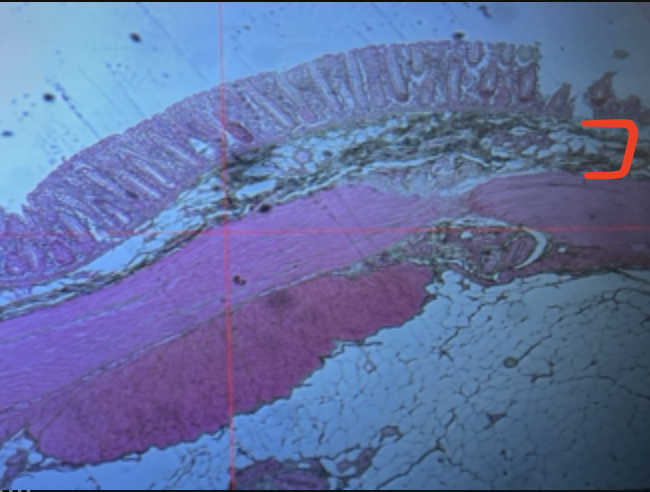

jejunum

villi

intestinal crypts

lumen

mucosa

mucosal epithelium

lamina propria

muscularis mucosa

submucosa

muscularis (externa)

serosa/adventitia